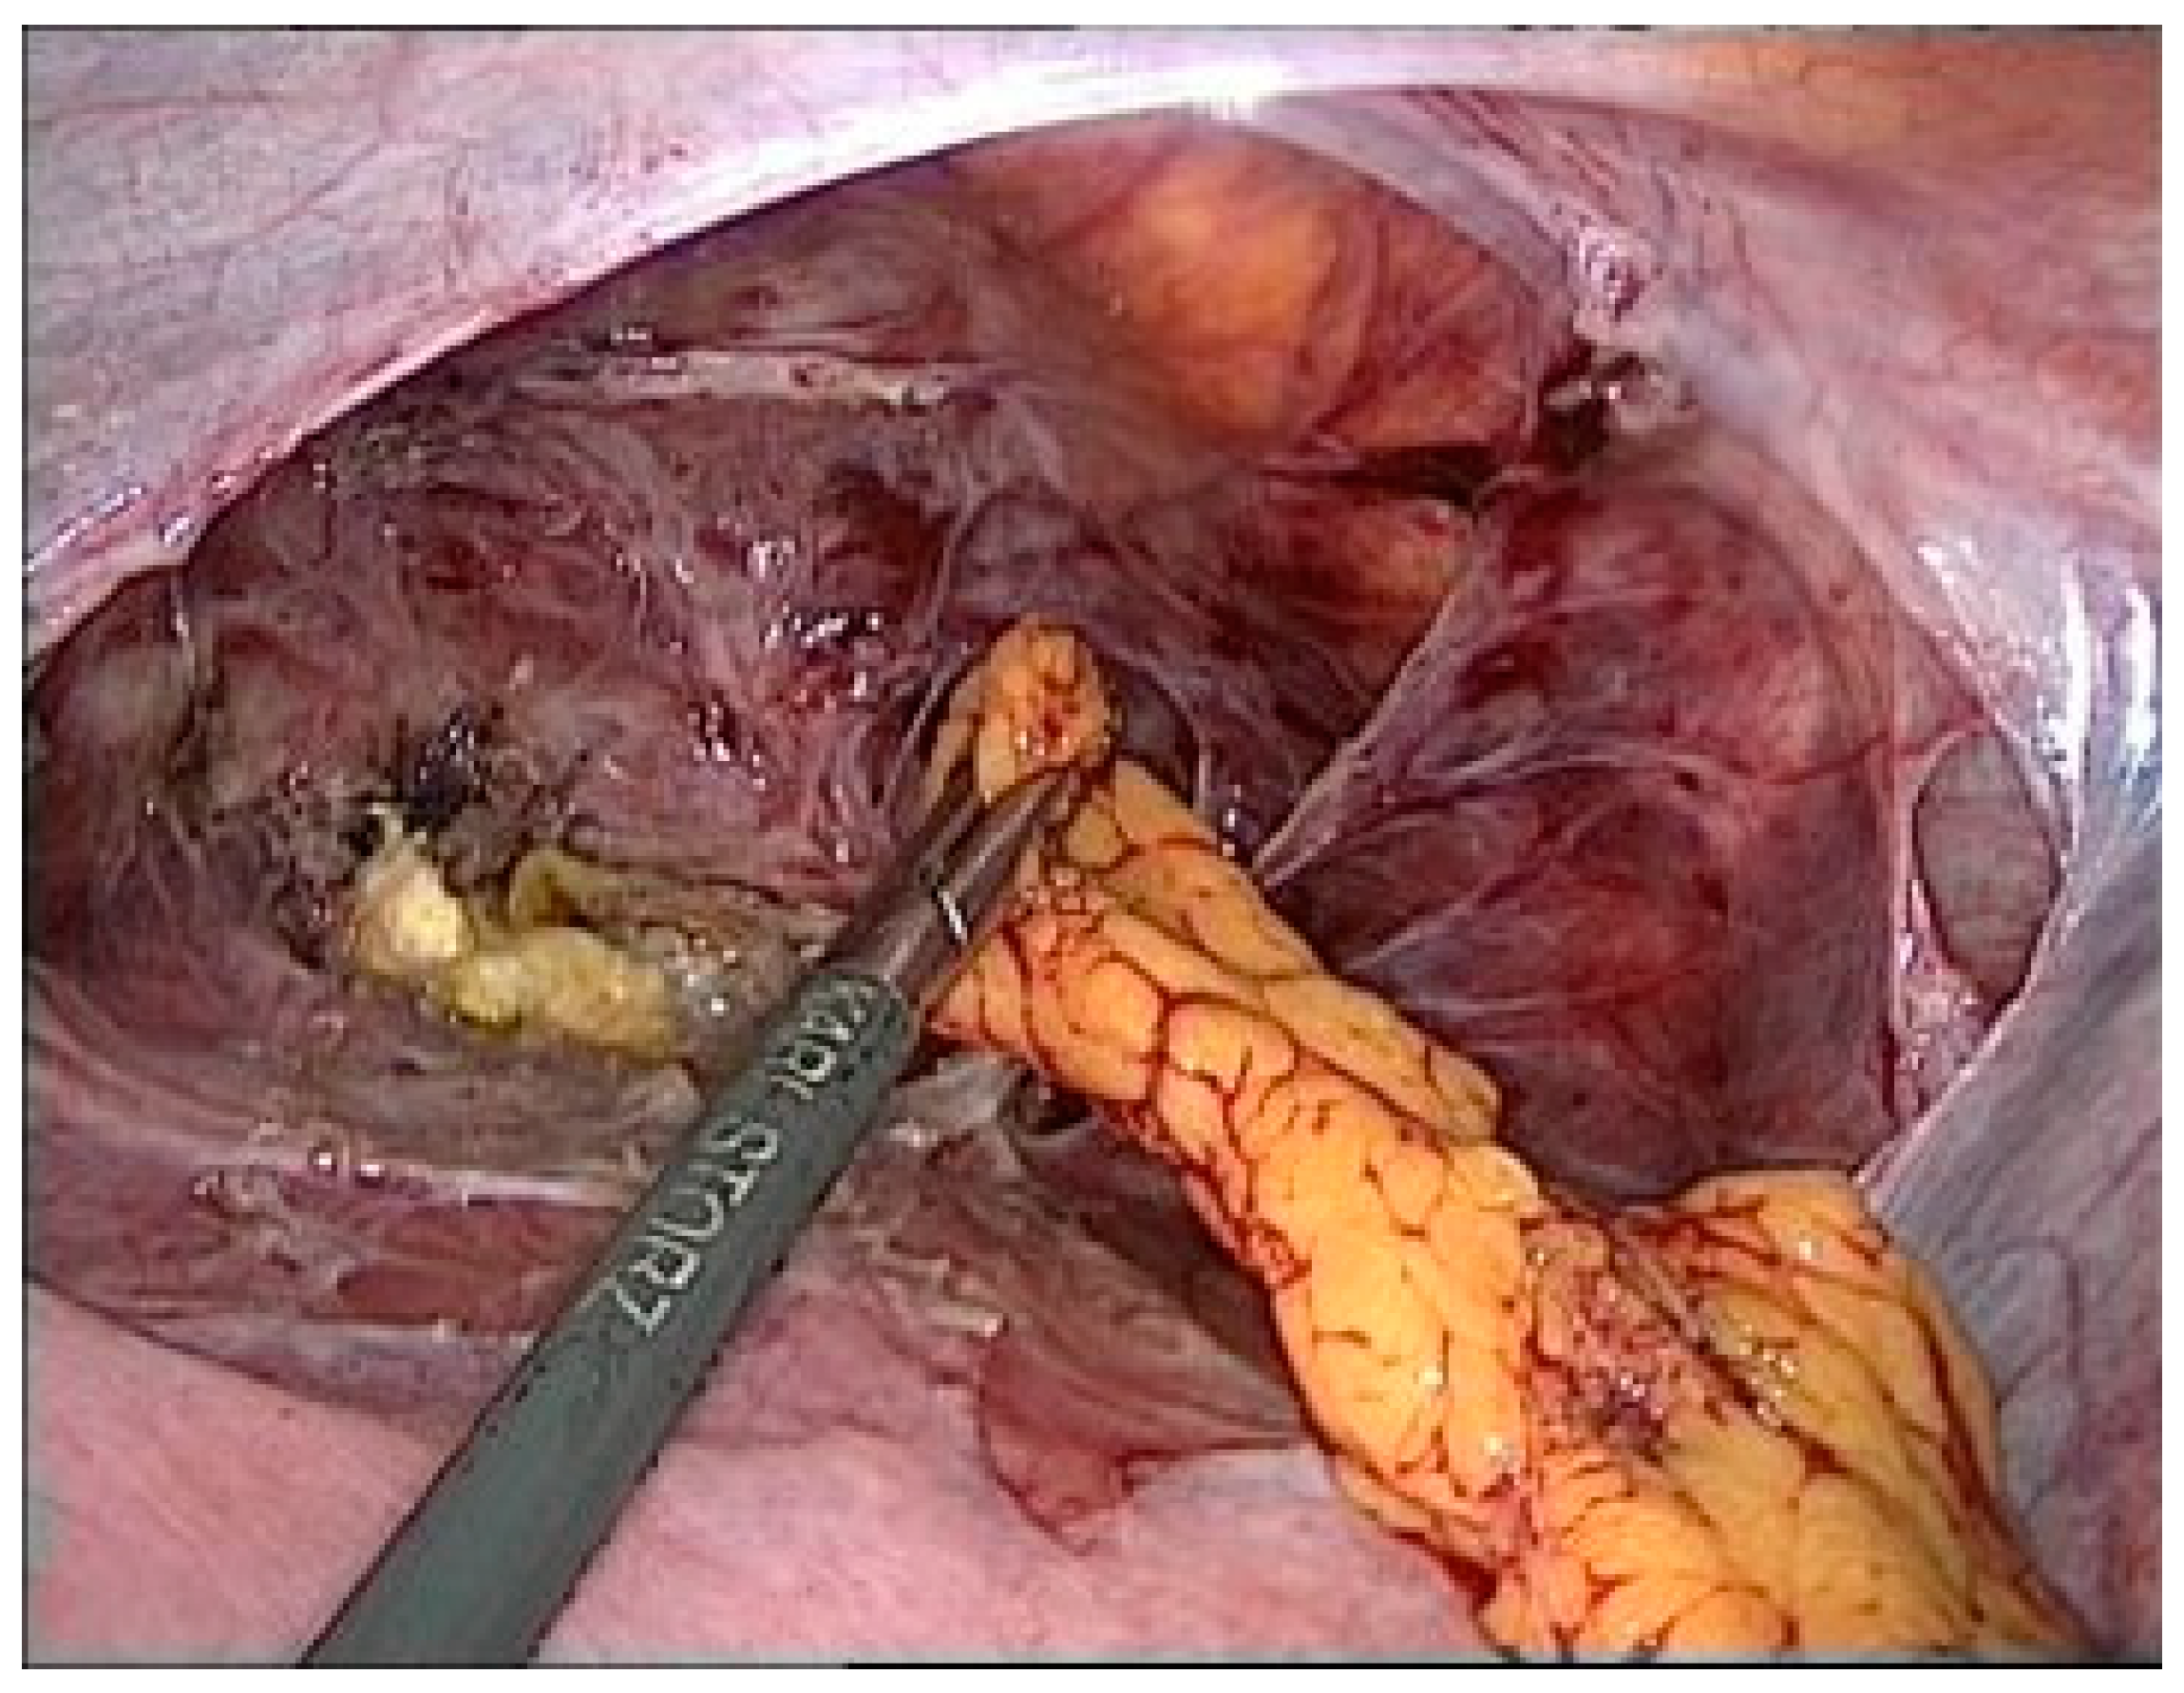

An Omentum flap was placed between the uterine body and bladder. The flap was carefully sutured to provide additional support and to promote healing (Figure 4).

Figure 4.

Omentum plastic.